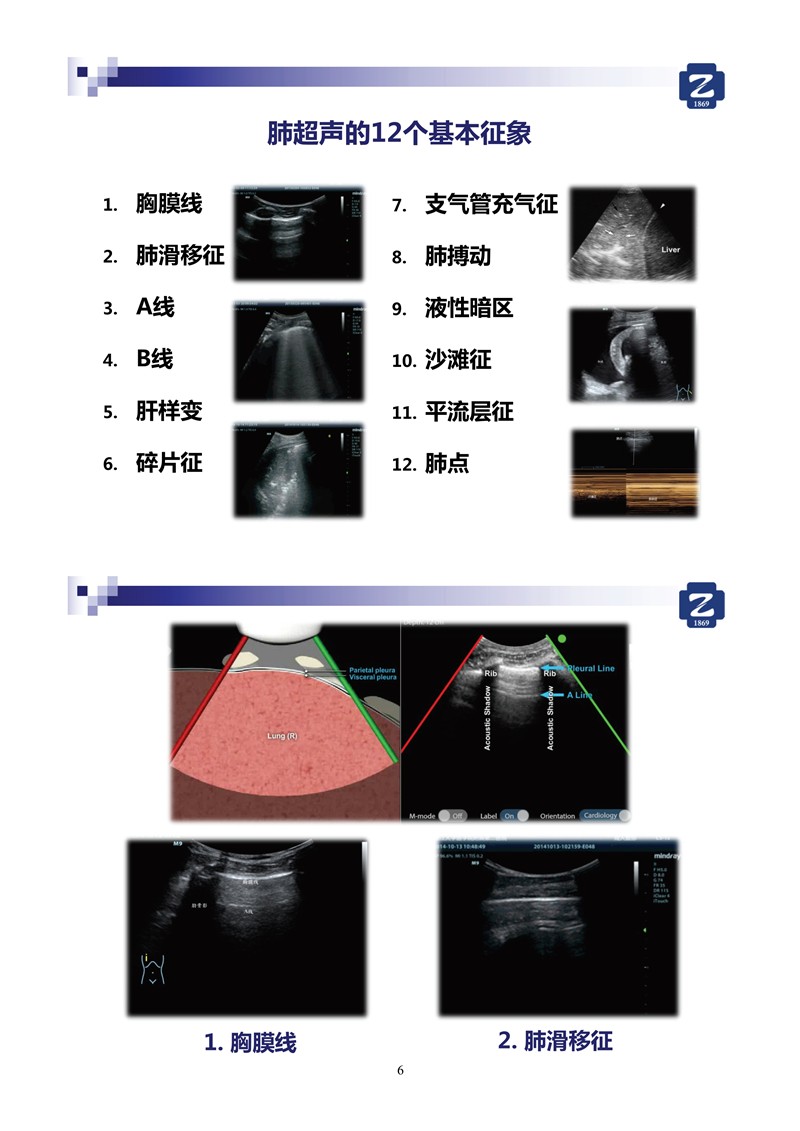

第二版新型冠狀病毒肺炎超聲診斷實(shí)用手冊(cè)_2.jpg